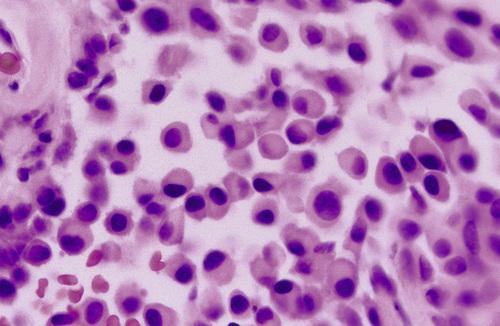

Parotid tumor demonstrating sheet of granular, basophilic serous acinar cells. The most characteristic cell is one with features of the serous acinar cell, with abundant granular basophilic cytoplasm and a round, darkly stained eccentric nucleus.

acinic cell carcinoma

High-power view of serous cells with basophilic, granular cytoplasm. The most characteristic cell is one with features of the serous acinar cell, with abundant granular basophilic cytoplasm and a round, darkly stained eccentric nucleus.

acinic cell carcinoma